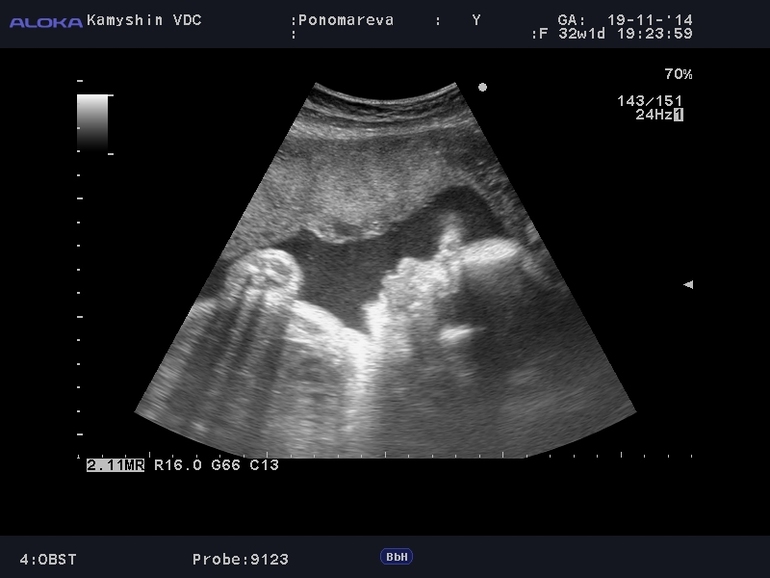

32 недели!!!

С сыном живот был раза в два больше))) или так кажется)))) но хотя все кто помнит меня беременной 12 лет назад говорят что сейчас животик меньше) ну а по весу набираю нисколько не меньше!!!! печалька((((

3 скрининг!!!! все ок))))

Ну вот и дождались мы третьего скрининга!!!!! Хотела снова 3Д делать, но не судьба!!! У нас поблизости нет нигде, а где есть туда ехать 250 км. Папа наш уехал на работу, а сама я не рискнула ехать так далеко!!! Жалко что во второй скрининг запись запороли(((

Вот такие мы уже ляльки)))

Ездили на УЗИ с сынулей))) Ему очень понравилось, все разглядел все понял)))) Для папы записали видео))))

Все параметры у нас в норме, сердечко работает как часики, воды в норме и весим мы уже 1600 гр))))